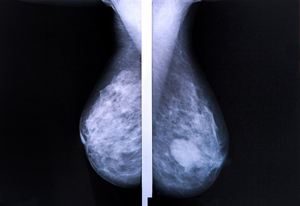

mammogram grVoor een aantal types van kanker raadt de overheid systematische screening aan. Bijvoorbeeld een mammografie voor vrouwen tussen 50 en 69 jaar om borstkanker op te sporen, een uitstrijkje bij vrouwen tussen 25 en 65 jaar om te controleren op baarmoederhalskanker en een screening naar colorectale kanker aan de hand van de stoelgang bij iedereen tussen 50 en 74 jaar. Uit de enquête van Test-Aankoop blijkt dat de bevolking erg losjes omspringt met de aanbevelingen van de overheid. Zo liet 21% van de vrouwen al een uitstrijkje nemen voor ze 20 jaar werden en maar liefst 72% van de vrouwen onderging al voor hun 50ste verjaardag een mammografie. 40% liet al een stoelganganalyse uitvoeren voor de aanbevolen leeftijd van 50 jaar. “De angst een bepaalde kanker te ontwikkelen, is een belangrijke drijfveer om een screening aan te vragen. Driekwart van de ondervraagden hoopt via screening de ziekte in een vroeg stadium te kunnen opsporen. De andere 26% hoopt de zekerheid te krijgen dat ze die ziekte niet zullen krijgen. Onderzoeken in het kader van een screening worden zelfs gezien als belangrijke maatregel om gezond te blijven. 66% van de ondervraagden vindt een jaarlijks bloedonderzoek belangrijker om gezond te blijven dan gezond eten en voldoende bewegen.”